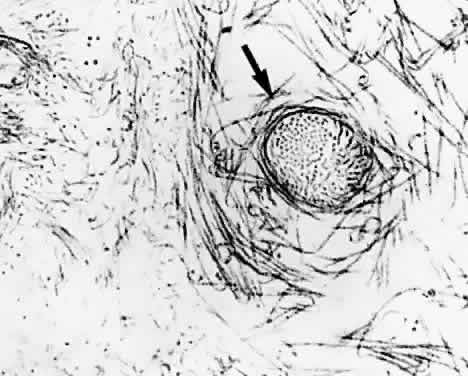

HA-collagen interaction in vitreous may be mediated by a third molecule.96 Studies by Hong and Davison97 have identified a type II procollagen in the soluble fraction of rabbit vitreous and raised the question of a possible role for this molecule in mediating collagen-HA interaction. Measurements of the dynamic viscoelasticity of bovine vitreous showed that the shapes of the master relaxation curves of the vitreous body are similar to those of lightly cross-linked polymer systems.98 Notably, the behavior of these relaxation curves is different from those observed in solutions of HA and collagen. This suggests that the physicochemical properties of vitreous in vivo are not simply the result of a combination of these two molecular elements, but that HA and collagen form a lightly cross-linked polymer system. Swann and colleagues99 have demonstrated large amounts of noncollagenous protein associated with collagen in the insoluble residue fraction of vitreous. Asakura40 studied bovine vitreous by ruthenium red staining and demonstrated the presence of amorphous structures on collagen fibrils at 55- to 60-nm intervals along the fibrils that are believed to be HA (Fig. 4). Filaments connect the collagen fibrils and these amorphous masses. These filaments may represent link structures that are either proteoglycans or a glycoprotein, such as hyaluronectin.100 In cartilage, link glycoproteins have been identified that interact with proteoglycans.101 Supramolecular complexes of these glycoproteins are thought to occupy the interfibrillar spaces in cartilage and may have a similar role in vitreous. In the cornea, chondroitin sulfate, and keratan sulfate bridge the interfibrillar spaces and keep the fibrils at specified distances to achieve transparency.102 This is clearly important in vitreous as well, where HA could bind to collagen fibrils by such linkage molecules, most probably in a repeating order. This type of arrangement would bind collagen fibrils to the protein core of a proteoglycans, such as chondroitin sulfate, as described by Asakura,40 keratan sulfate, or both, as in the cornea, and would organize the network in a manner to keep the vitreous collagen fibrils apart by at least one wavelength of incident light, the critical distance needed to minimize light scattering. Although such supramolecular organization to maintain vitreous transparency was proposed41 more than a decade ago, no evidence has yet been generated.

Fig. 4. Ultrastructure of vitreous collagen-hyaluronan (HA) interaction. The specimen was fixed in glutaraldehyde/paraformaldehyde and stained with ruthenium red. The collagen fibrils (C) are coated with an amorphous material (A) that is believed to be HA. The amorphous material may connect to the collagen fibril by another GAG, possibly chondroitin sulfate (see inset, lower right). Interconnecting filaments (IF) appear to bridge between collagen fibrils, inserting or attaching at sites of hyaluronan adhesion to the collagen fibrils. Bar = 0.1 μm. (From Asakura A. Histochemistry of hyaluronic acid of the bovine vitreous body as studied by electron microscopy. Acta Soc Ophthalmol Jpn 89:179, 1985, with permission)